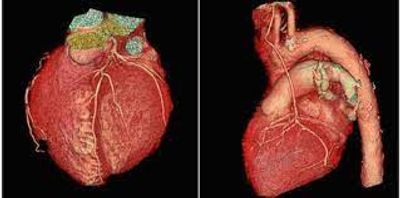

FOR ACQUISITION OF THE CCTA ENSURE THE SMALLEST FOV POSSIBLE TO ENSURE THE BEST SPACIAL RESOLUTION. SCAN SHOULD EXTEDND FROM THE CARINA THROUGH THE APEX OF THE HEART (SHOWN BELOW)

IMPORTANT DETAIL: IF THE PAITENT HAS A HISTORY OF CARDIAC STENTS/CABG SCAN SHOULD START FROM THE THORACIC INLET THROUGHT THE APEX OF THE HEART. MAKE SURE TO DOCUMENT THIS IN YOUR TECH NOTES.